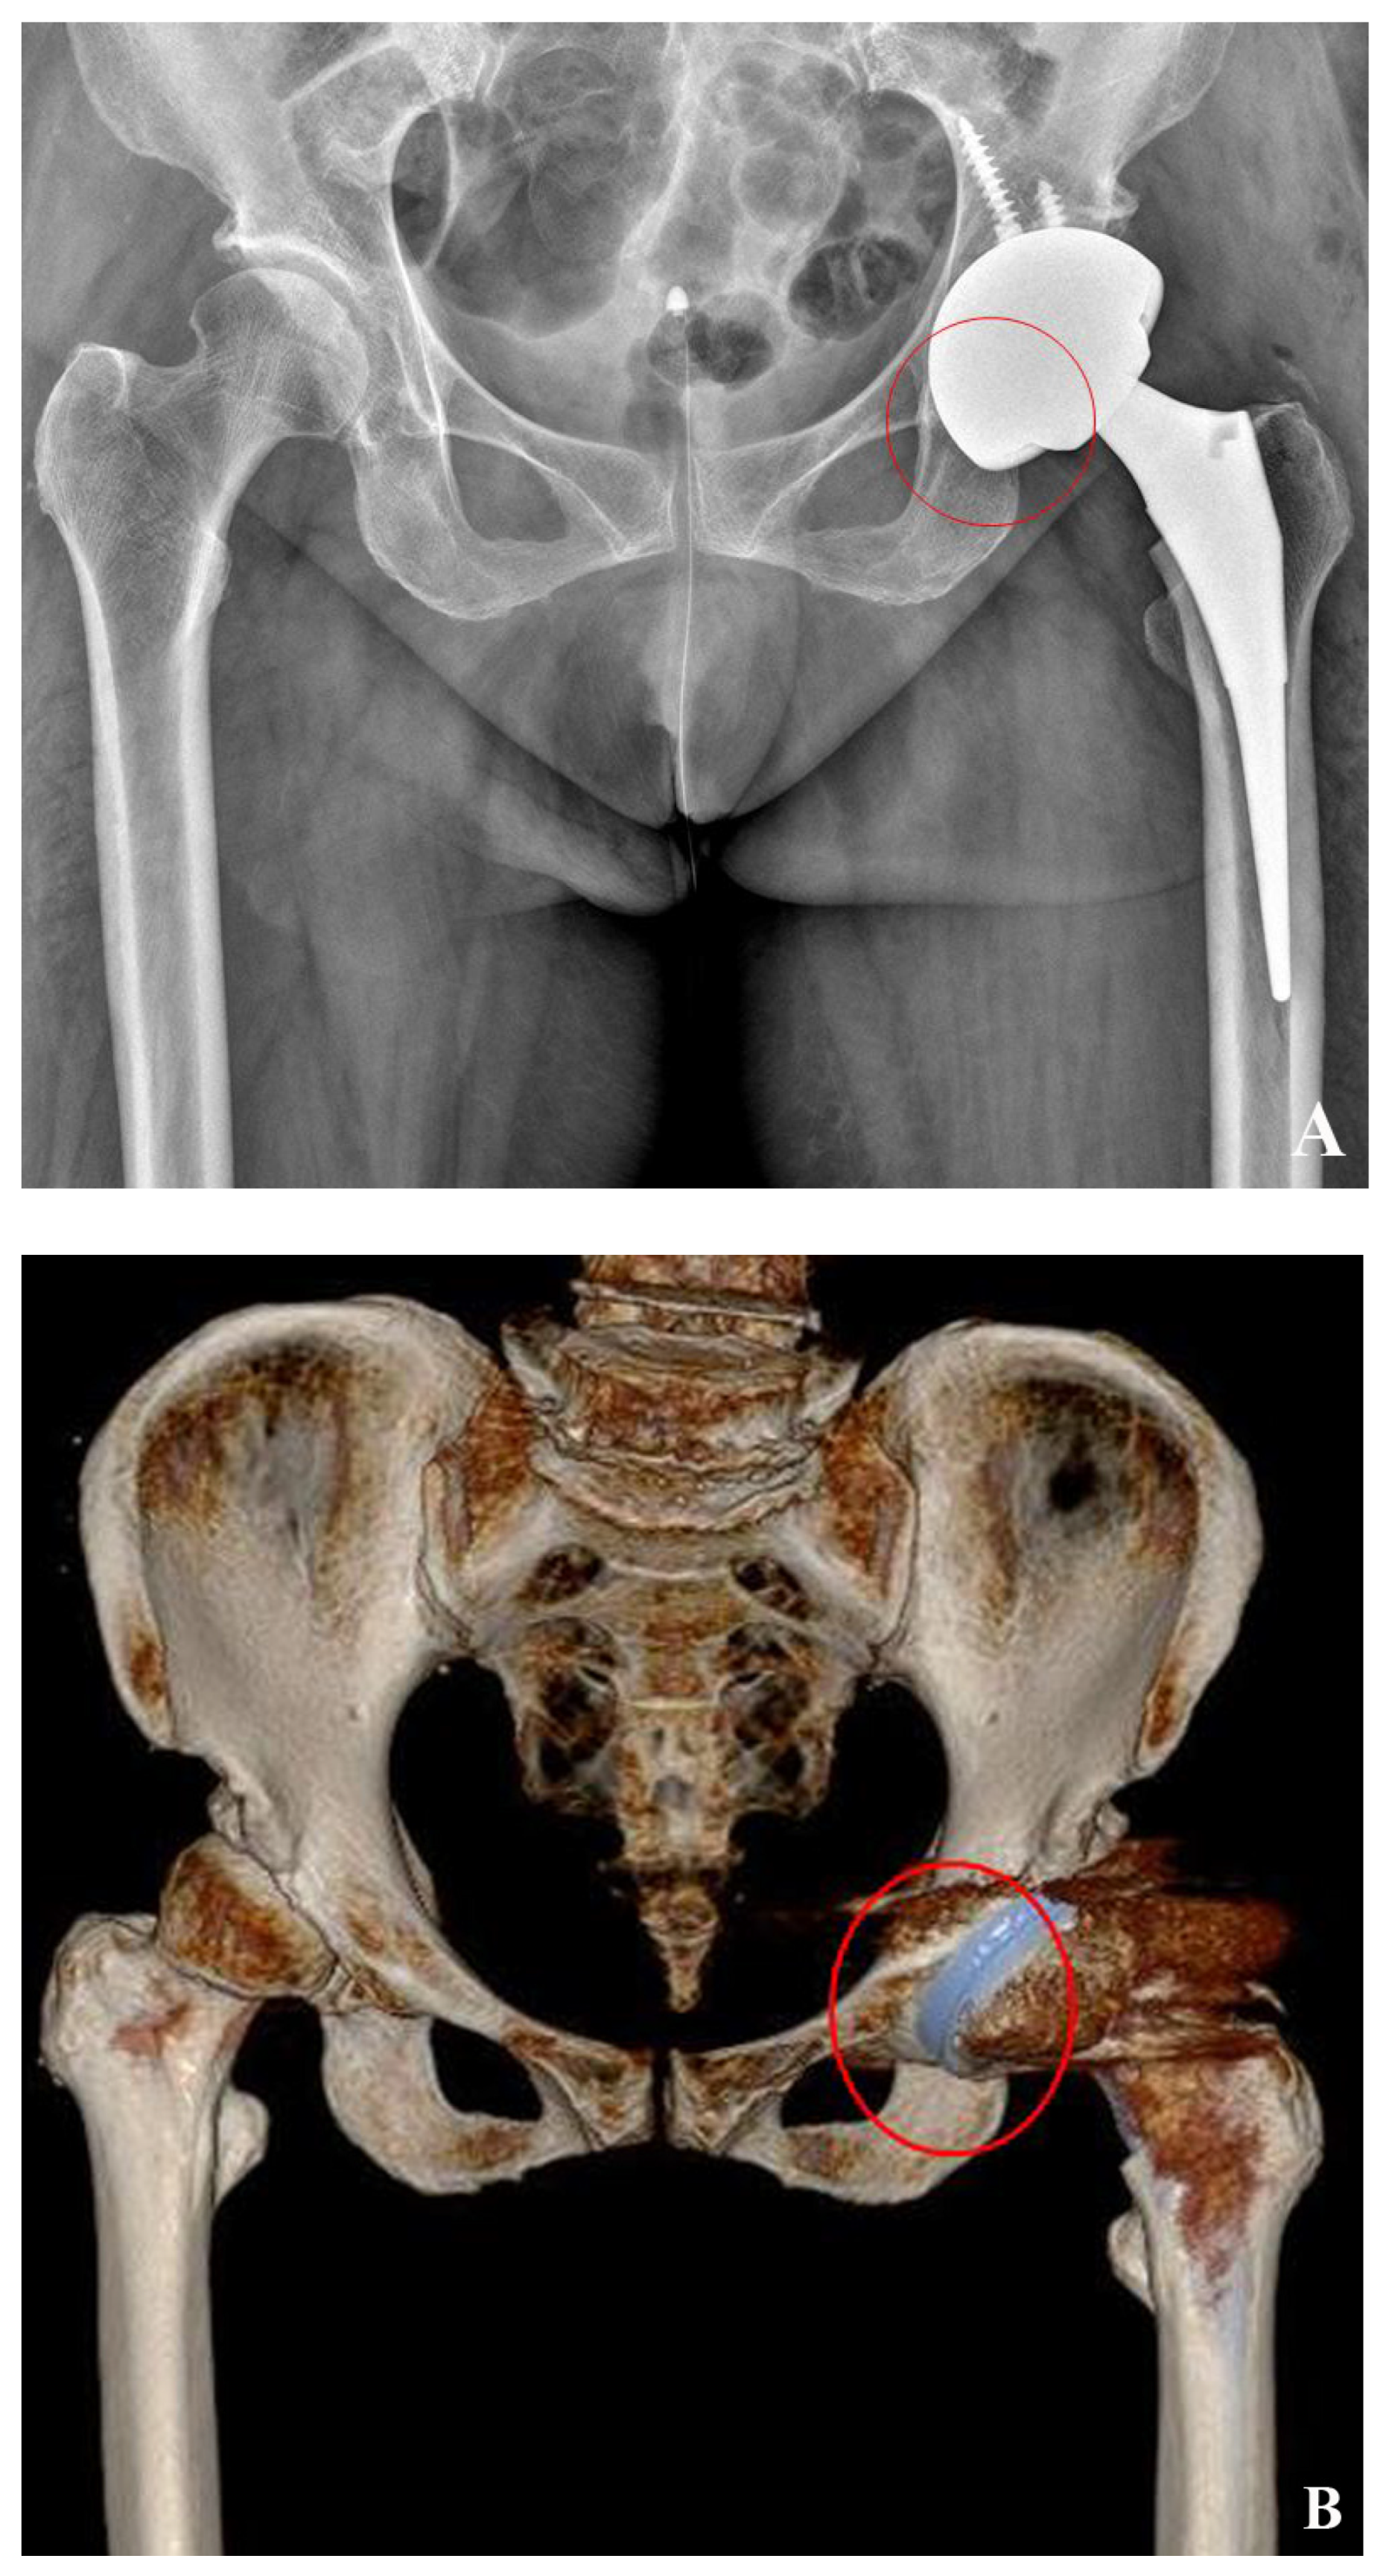

2.4. Cup Position and Fixation

2.6. 3D-Based Measurement of Host Bone Coverage from CT Scans

2.7. Measurement of Intra-Operative Host Bone Coverage